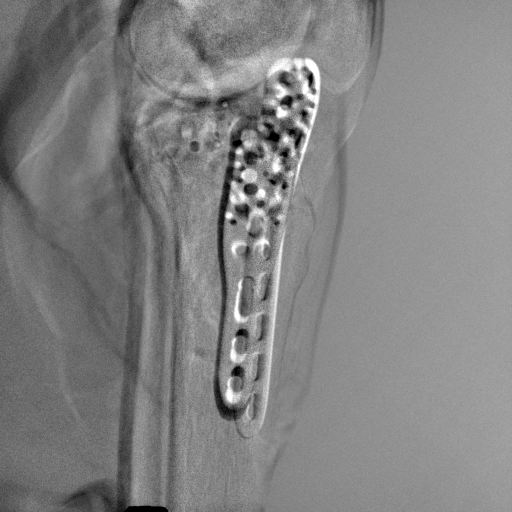

5.4 Real Knee Data with Metal Implants

Refer to caption

Figure 13: Three examples of synthetic perspective projection images for training, intensity window: [0, 4]. The appearance (e.g., image contrast and metal image resolution) of such DRR training images is different from that of real projection images in Fig. 14.

0superscript00^{\circ} perspective

[Uncaptioned image]

(a) 32.56, 109.85

(b) 18.91, 19.54

180superscript180180^{\circ} perspective

(c) 28.11, 112.16

(d) 15.80, 19.27

View difference

0superscript00^{\circ} and 180superscript180180^{\circ} RGB

DRR reference

(e) 29.72, 111.80

(f) 17.14, 19.38

Pix2pixGAN

(g) 29.72, 111.80

(h) 17.50, 19.70

(Fig. 14 continues in the next column.)

TransU-Net

(i) 29.72, 111.80

(j) 16.23, 19.25

Figure 14: The results for the real cadaver leg data. The green dots mark the positions of landmarks in the corresponding reference images. In the first column, the arrows indicate the bone cavity/fracture structures. In the second column, the solid lines mark the widths and heights of the metals. The green ones are measured from the DRR reference, while the red ones are measured in the corresponding perspective projection image. In the last column, the lines mark the centerlines of the metal screws, where the green lines are those from the reference image. The lengths of the lines in mm are displayed in their corresponding subcaptions. Intensity window: [0, 4]. Please zoom in for better visualization.

The complementary view setting for learning perspective deformation is also evaluated on real CBCT projection data. In this evaluation, real CBCT projection data from a dataset of knees with metal implants is used for testing, while DRRs created from volumetric CT datasets with inserted metals is used for training. Three exemplary DRR perspective projection images for training are displayed in Fig. 13, in which synthetic metal implants are inserted [34]. The appearance, e.g., image contrast and metal image resolution, of such DRR training images is different from that of real projection images in Fig. 14. In Fig. 14, the results for three knees, with and without metal implants, are displayed. The first and second rows are the 0superscript00^{\circ} and 180superscript180180^{\circ} perspective projections, respectively, rebinned to the virtual detector with geometric calibration based on their respective principal points and projections of the world origin. The third row displays their difference images, where the magnitude of deviation increases from the center towards the outside like it does in DRRs with an ideal scan trajectory (e.g., Fig. 6(e)), although real projection data suffer from various physical effects like beam hardening and Poisson noise. The fourth row displays the RGB stacks of 0superscript00^{\circ} and 180superscript180180^{\circ} perspective projection images. The magenta and green regions indicate structures with considerable perspective deformation, for example, the knee patella in Fig. 5.4, the top parts of the two metals in Fig. 5.4, and the bottom two screws in Fig. 5.4. The fifth row displays reference images, which are orthogonal projections of iterative reconstruction volumes from measured CBCT projection data. In the reference images, a total of five landmarks are selected, with the positions being marked by the green dots: In Fig. 5.4, two positions at the edges of the knee patella are marked; In Fig. 14(e) and Fig. 14(f), one position at the left edge of the fibula is marked for each image. In addition, a rectangular frame for the two metals is marked by the green dashed lines, while its width and height are indicated by the green solid lines, which are 29.71 mm and 111.99 mm, respectively. In Fig. 14(f), the centerlines of the bottom two screws are sketched by the green lines, which have the lengths of 17.14 mm (middle screw) and 19.38 mm (bottom screw). The corresponding rectangular frame for the two metals and the screw centerlines in the perspective projection images are marked as well, but in red color. In Fig. 14(a), the width and height of the metals are 32.56 mm and 109.85 mm, which have deviations of 2.84 mm and -1.95 mm to the reference ones, respectively. In Fig. 14(b), the centerline lengths are 18.91 mm and 19.54 mm, which have deviations of 1.77 mm and 0.16 mm, respectively. Although the bottom screw has little length deviation to the reference, the orientations of both screws are obviously deviated. The sixth row shows the results of Pix2pixGAN using 0superscript00^{\circ} and 180superscript180180^{\circ} polar inputs. For all of the landmarks, the green reference dots are all located accurately in the Pix2pixGAN images. The rectangular reference frame also accurately covers the metals in Fig. 14(g). In Fig. 14(h), although the two red centerlines do not exactly overlap with the green one, they are very close in lengths and orientations. Please zoom in for better visualization.